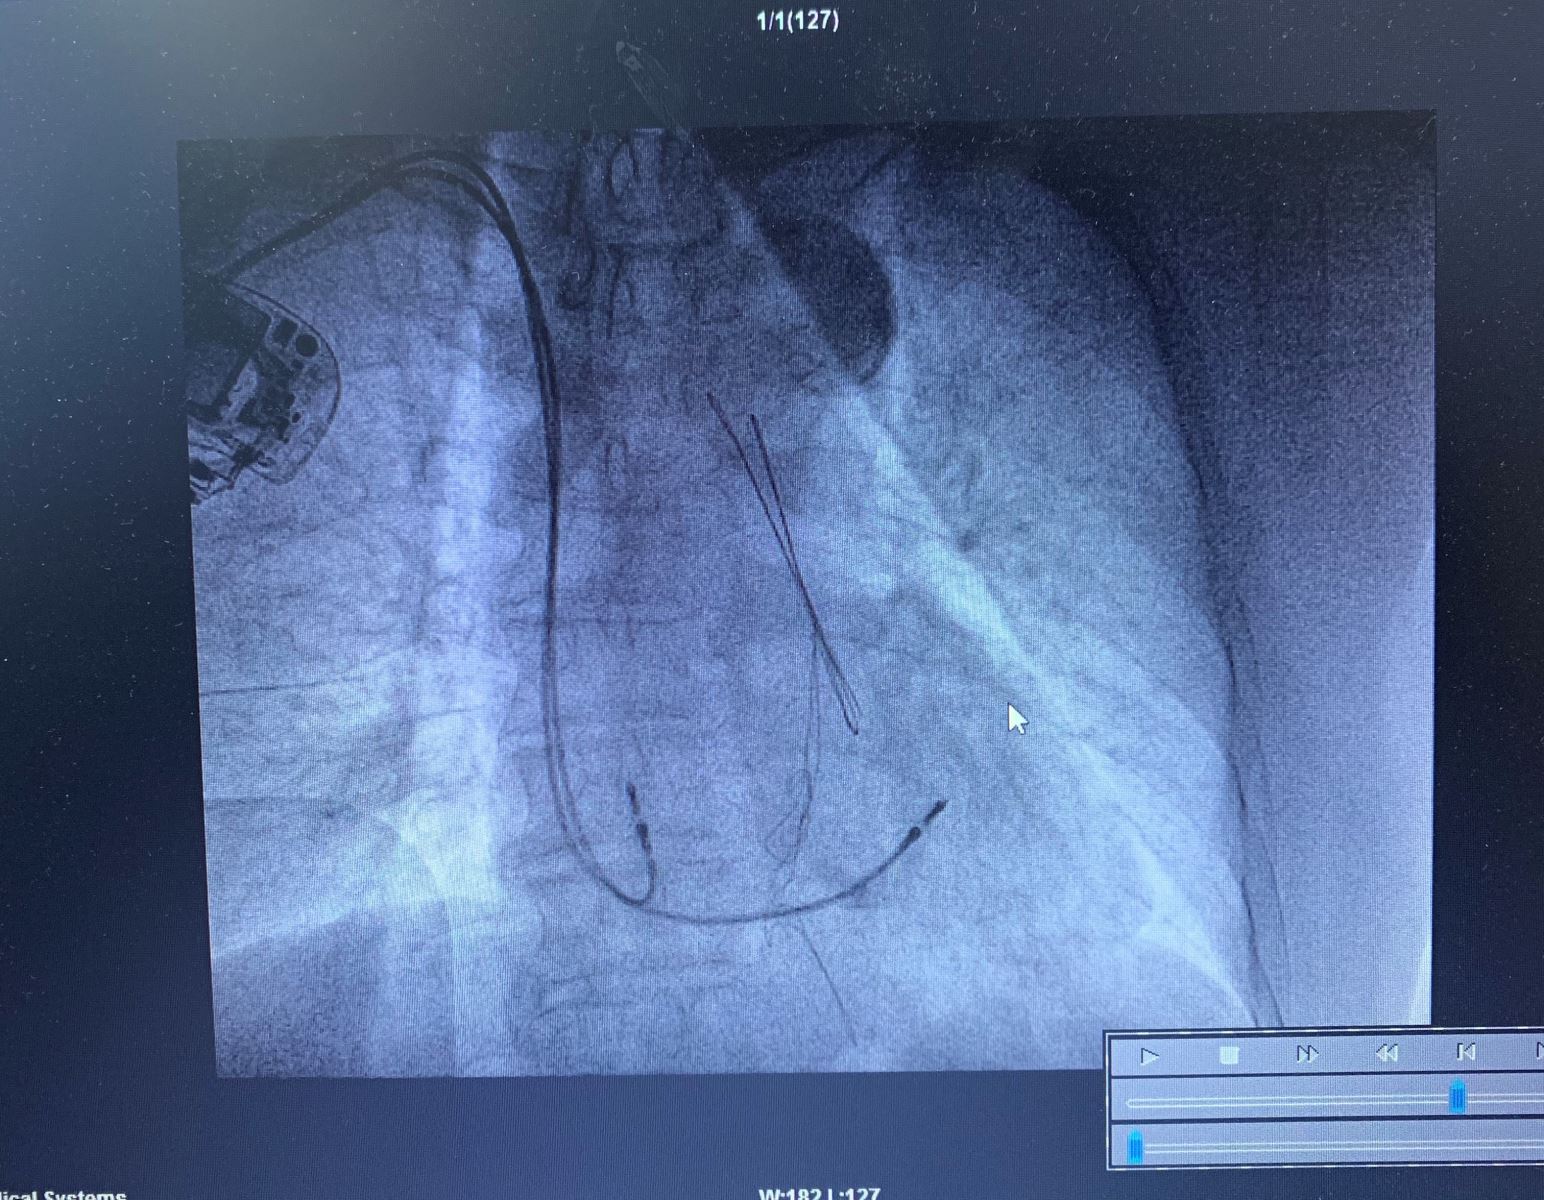

近日,我院心血管内三科团队成功为一名高龄严重心律失常伴脑血管病患者实施了抗核磁共振永久心脏起搏器植入术,解决了戴起搏器无法接受核磁共振检查的问题,该项技术在我院尚属首例。术后患者恢复良好,于1月6日顺利康复出院。

患者为一位92岁的男性患者,近来反复出现晕厥、目眩、头痛伴心悸不适等症状来我院就诊治疗。入院后行24小时动态心电图(Holter)检查,显示患者心脏多次停博数秒钟,最长停博时间长达近8秒,诊断为心律失常—高度房室传导阻滞,病情危重,必须马上安装永久性心脏起搏器。但考虑到患者有10余年高血压、脑血管病史,病情发展有需要核磁共振(MRI)检查的可能,不宜安装普通心脏起搏器。心内三科杜建军主任与患者及家属进行充分沟通后,决定为患者安装一枚能抗核磁干扰的新型起搏器。

2019年12月25日,历经1个多小时的精心手术,起搏器植入成功,患者心率恢复正常,无黑蒙及头晕等不适症状发作。